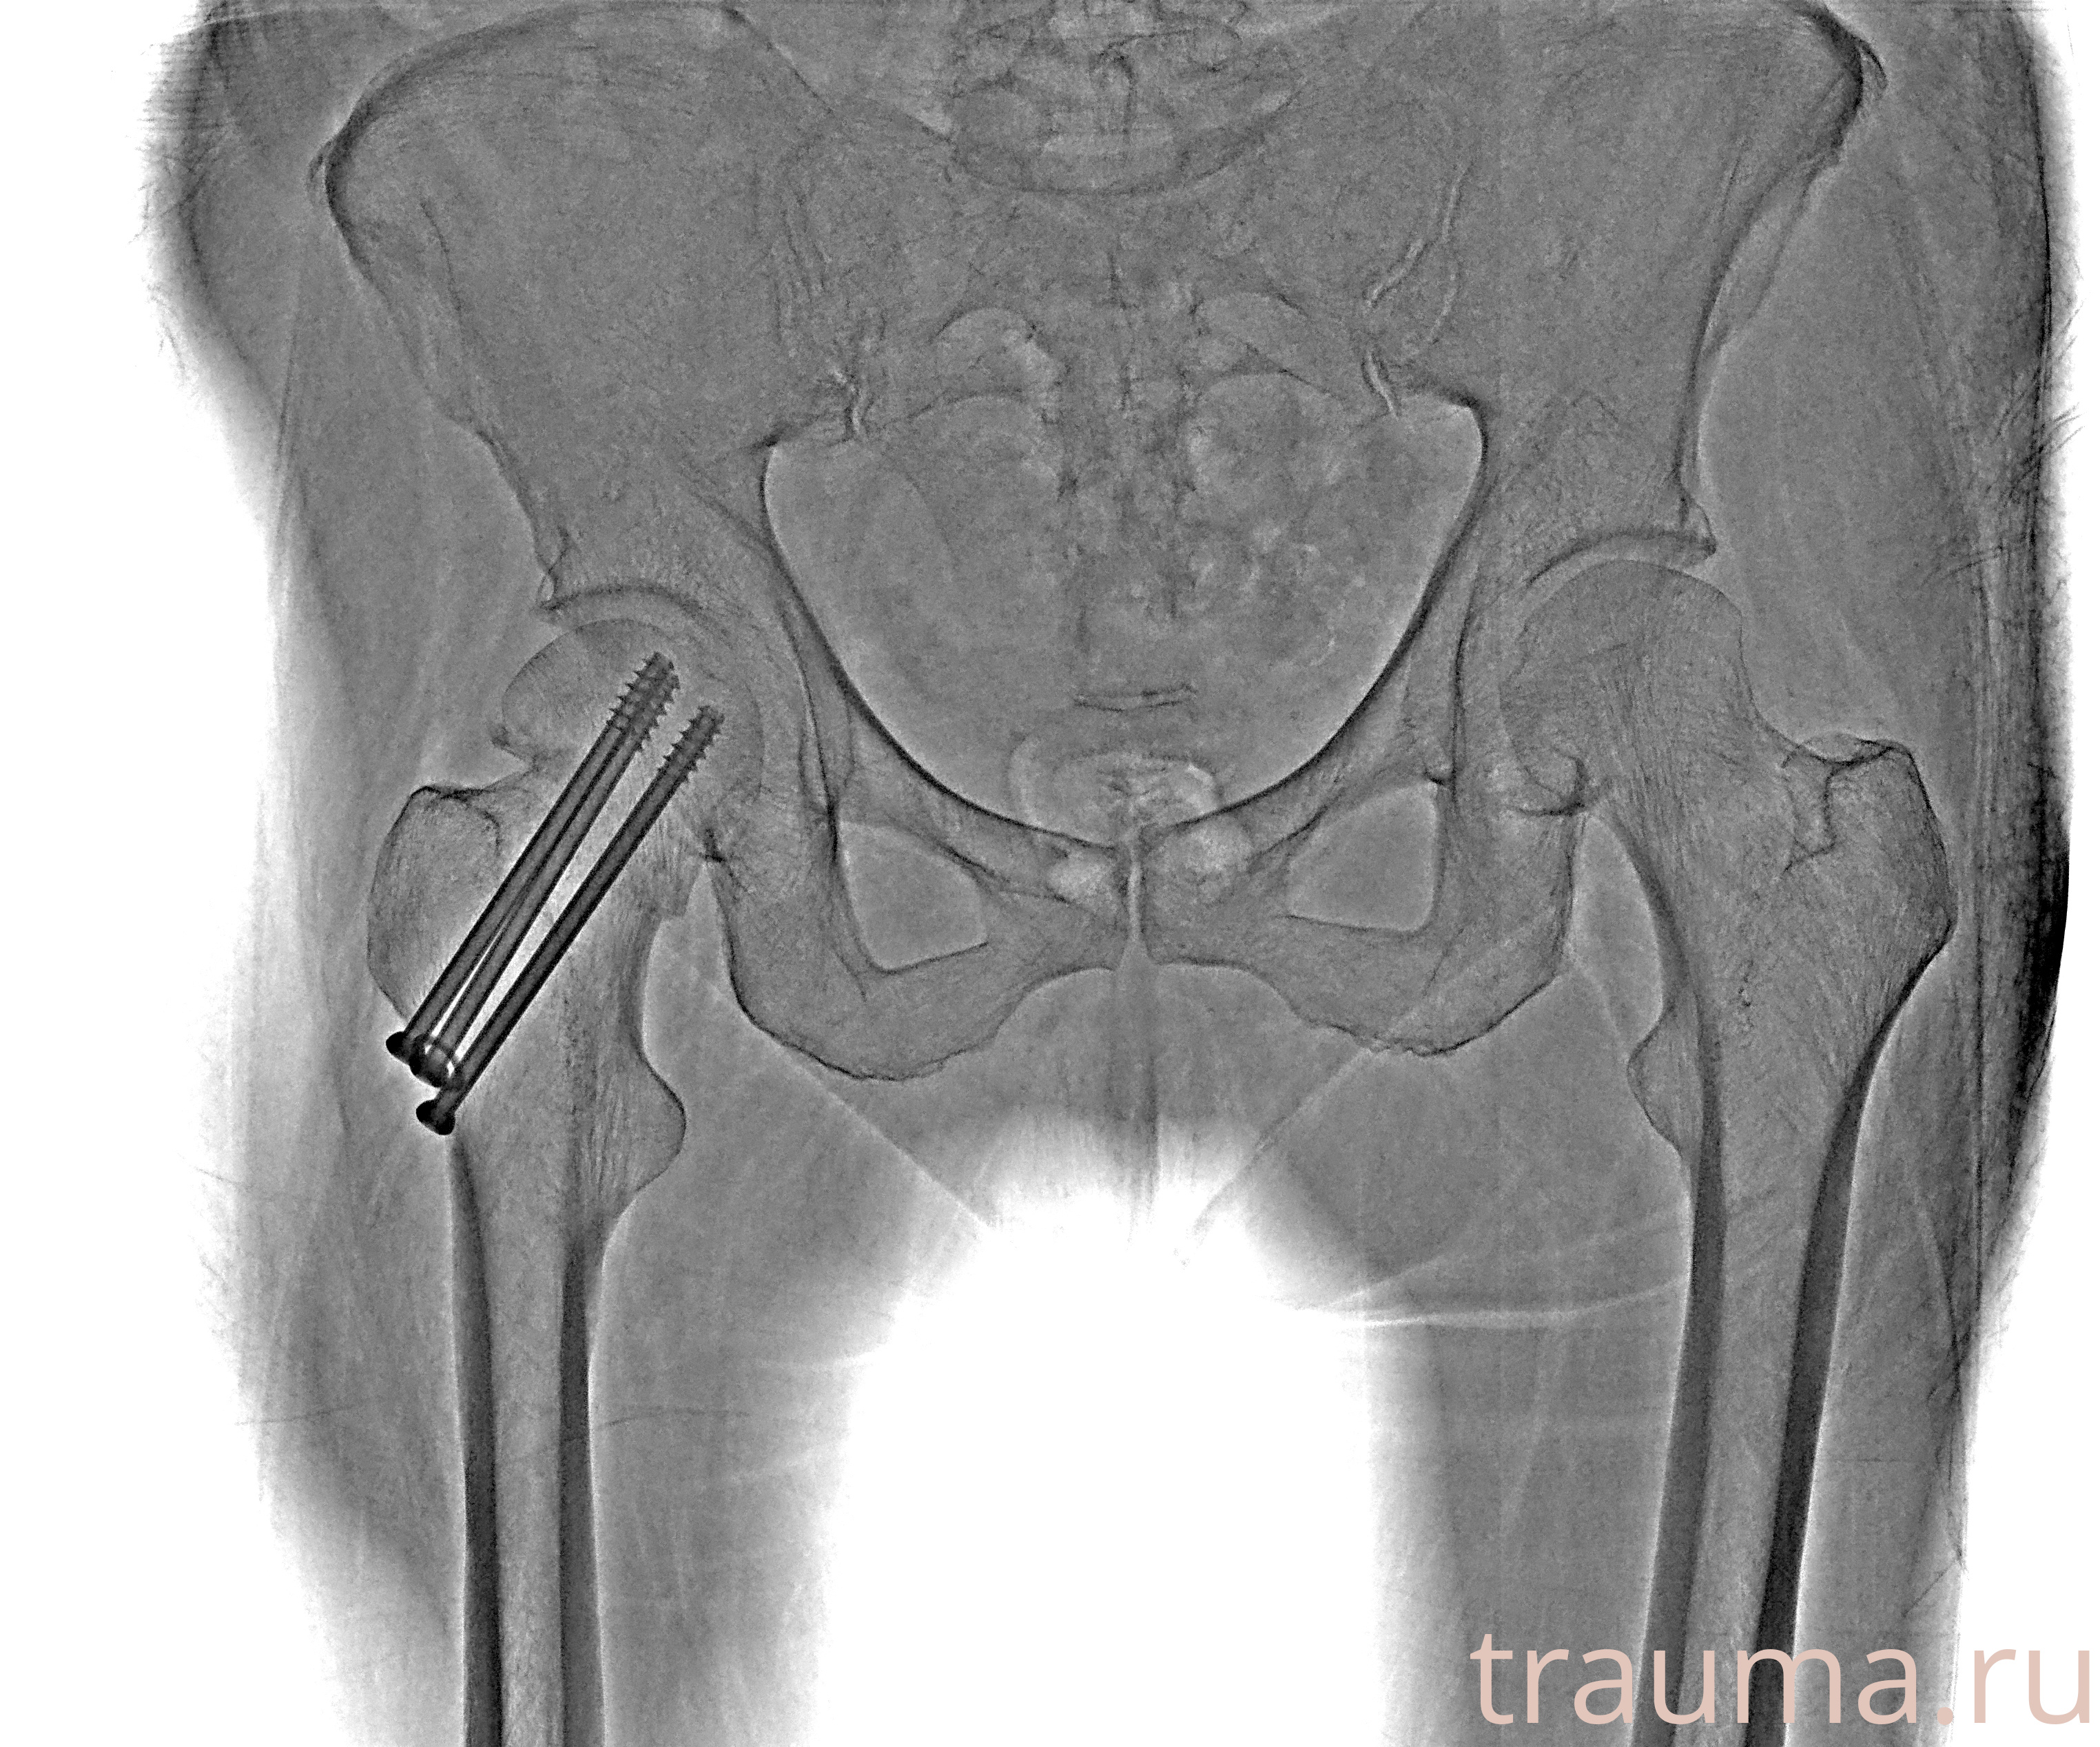

Рентгенограммы

Рентген на дому: по вашему адресу приезжает врач-рентгенолог, травматолог-ортопед с мобильным рентгеновским аппаратом, проводит диагностику травмы или заболевания, делает необходимые рентгенограммы, дает рекомендации по дальнейшему лечению. Получить качественные снимки в домашних условиях возможно благодаря уникальной методике, разработанной МосРентген Центром для института  Склифосовского